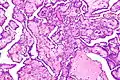

Histological features of normal cells and cancer cells

Cancer cells have distinguishing histological features visible under the microscope. The nucleus is often large and irregular, and the cytoplasm may also display abnormalities.[3]

The shape, size, protein composition, and texture of the nucleus are often altered in malignant cells. The nucleus may acquire grooves, folds or indentations, chromatin may aggregate or disperse, and the nucleolus can become enlarged. In normal cells, the nucleus is often round or solid in shape, but in cancer cells the outline is often irregular. Different combinations of abnormalities are characteristic of different cancer types, to the extent that nuclear appearance can be used as a marker in cancer diagnostics and staging.[4]